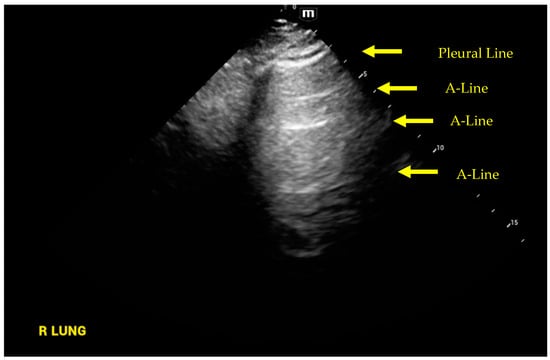

4. Lung Ultrasound

- Volpicelli, G.; Elbarbary, M.; Blaivas, M.; Lichtenstein, D.A.; Mathis, G.; Kirkpatrick, A.W.; Melniker, L.; Gargani, L.; Noble, V.E.; Via, G.; et al. International evidence-based recommendations for point-of-care lung ultrasound. Intensive Care Med. 2012, 38, 577–591. [Google Scholar] [CrossRef]

- Rouby, J.J.; Arbelot, C.; Gao, Y.; Zhang, M.; Lv, J.; An, Y.; Chunyao, W.; Bin, D.; Valente Barbas, C.S.; Dexheimer Neto, F.L.; et al. Training for Lung Ultrasound Score Measurement in Critically Ill Patients. Am. J. Respir. Crit. Care Med. 2018, 198, 398–401. [Google Scholar] [CrossRef]

- Lichtenstein, D.A.; Meziere, G.A. Relevance of lung ultrasound in the diagnosis of acute respiratory failure: The BLUE protocol. Chest 2008, 134, 117–125. [Google Scholar] [CrossRef] [PubMed]

- Lichtenstein, D.; Meziere, G.; Biderman, P.; Gepner, A.; Barre, O. The comet-tail artifact. An ultrasound sign of alveolar-interstitial syndrome. Am. J. Respir. Crit. Care Med. 1997, 156, 1640–1646. [Google Scholar] [CrossRef]

- Agricola, E.; Bove, T.; Oppizzi, M.; Marino, G.; Zangrillo, A.; Margonato, A.; Picano, E. “Ultrasound comet-tail images”: A marker of pulmonary edema: A comparative study with wedge pressure and extravascular lung water. Chest 2005, 127, 1690–1695. [Google Scholar] [CrossRef]

- Lichtenstein, D.A.; Meziere, G.A.; Lagoueyte, J.F.; Biderman, P.; Goldstein, I.; Gepner, A. A-lines and B-lines: Lung ultrasound as a bedside tool for predicting pulmonary artery occlusion pressure in the critically ill. Chest 2009, 136, 1014–1020. [Google Scholar] [CrossRef] [PubMed]

- Noble, V.E.; Murray, A.F.; Capp, R.; Sylvia-Reardon, M.H.; Steele, D.J.R.; Liteplo, A. Ultrasound assessment for extravascular lung water in patients undergoing hemodialysis. Time course for resolution. Chest 2009, 135, 1433–1439. [Google Scholar] [CrossRef]

- Volpicelli, G.; Skurzak, S.; Boero, E.; Carpinteri, G.; Tengattini, M.; Stefanone, V.; Luberto, L.; Anile, A.; Cerutti, E.; Radeschi, G.; et al. Lung ultrasound predicts well extravascular lung water but is of limited usefulness in the prediction of wedge pressure. Anesthesiology 2014, 121, 320–327. [Google Scholar] [CrossRef] [PubMed]

- Enghard, P.; Rademacher, S.; Nee, J.; Hasper, D.; Engert, U.; Jorres, A.; Kruse, J.M. Simplified lung ultrasound protocol shows excellent prediction of extravascular lung water in ventilated intensive care patients. Crit. Care 2015, 19, 36. [Google Scholar] [CrossRef]

- Pivetta, E.; Goffi, A.; Lupia, E.; Tizzani, M.; Porrino, G.; Ferreri, E.; Volpicelli, G.; Balzaretti, P.; Banderali, A.; Iacobucci, A.; et al. Lung Ultrasound-Implemented Diagnosis of Acute Decompensated Heart Failure in the ED: A SIMEU Multicenter Study. Chest 2015, 148, 202–210. [Google Scholar] [CrossRef]

- Laursen, C.B.; Sloth, E.; Lassen, A.T.; Christensen, R.; Lambrechtsen, J.; Madsen, P.H.; Henriksen, D.P.; Davidsen, J.R.; Rasmussen, F. Point-of-care ultrasonography in patients admitted with respiratory symptoms: A single-blind, randomised controlled trial. Lancet Respir. Med. 2014, 2, 638–646. [Google Scholar] [CrossRef]